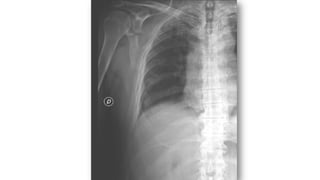

FRACTURA ESCAPULA

• Traumatismo directo de alta energía. Se asocia a otras

fracturas-luxaciones de C. escapular ó tórax

(neumotórax…)

• Si no se piensa en esta posible fractura es muy difícil

detectarla

• Si afecta a cuerpo o espina (50%), tratamiento

conservador

• Si se afecta cuello o glenoides: valorar cirugía

• Consolidan a las 6 semanas